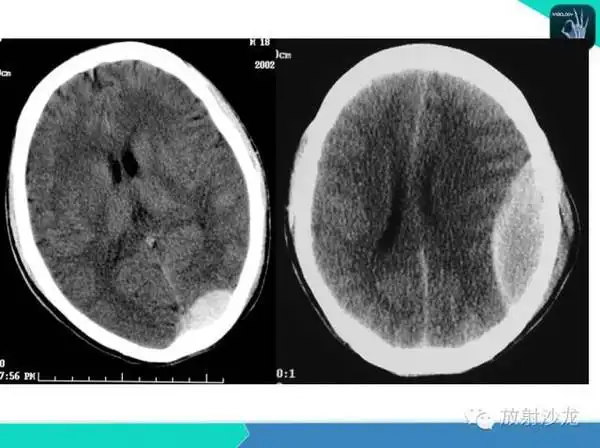

67超急性期大面积脑梗死ct平扫表现

图6. 2017年5月15日头颅ct显示脑沟脑池不清晰,脑肿胀明显.